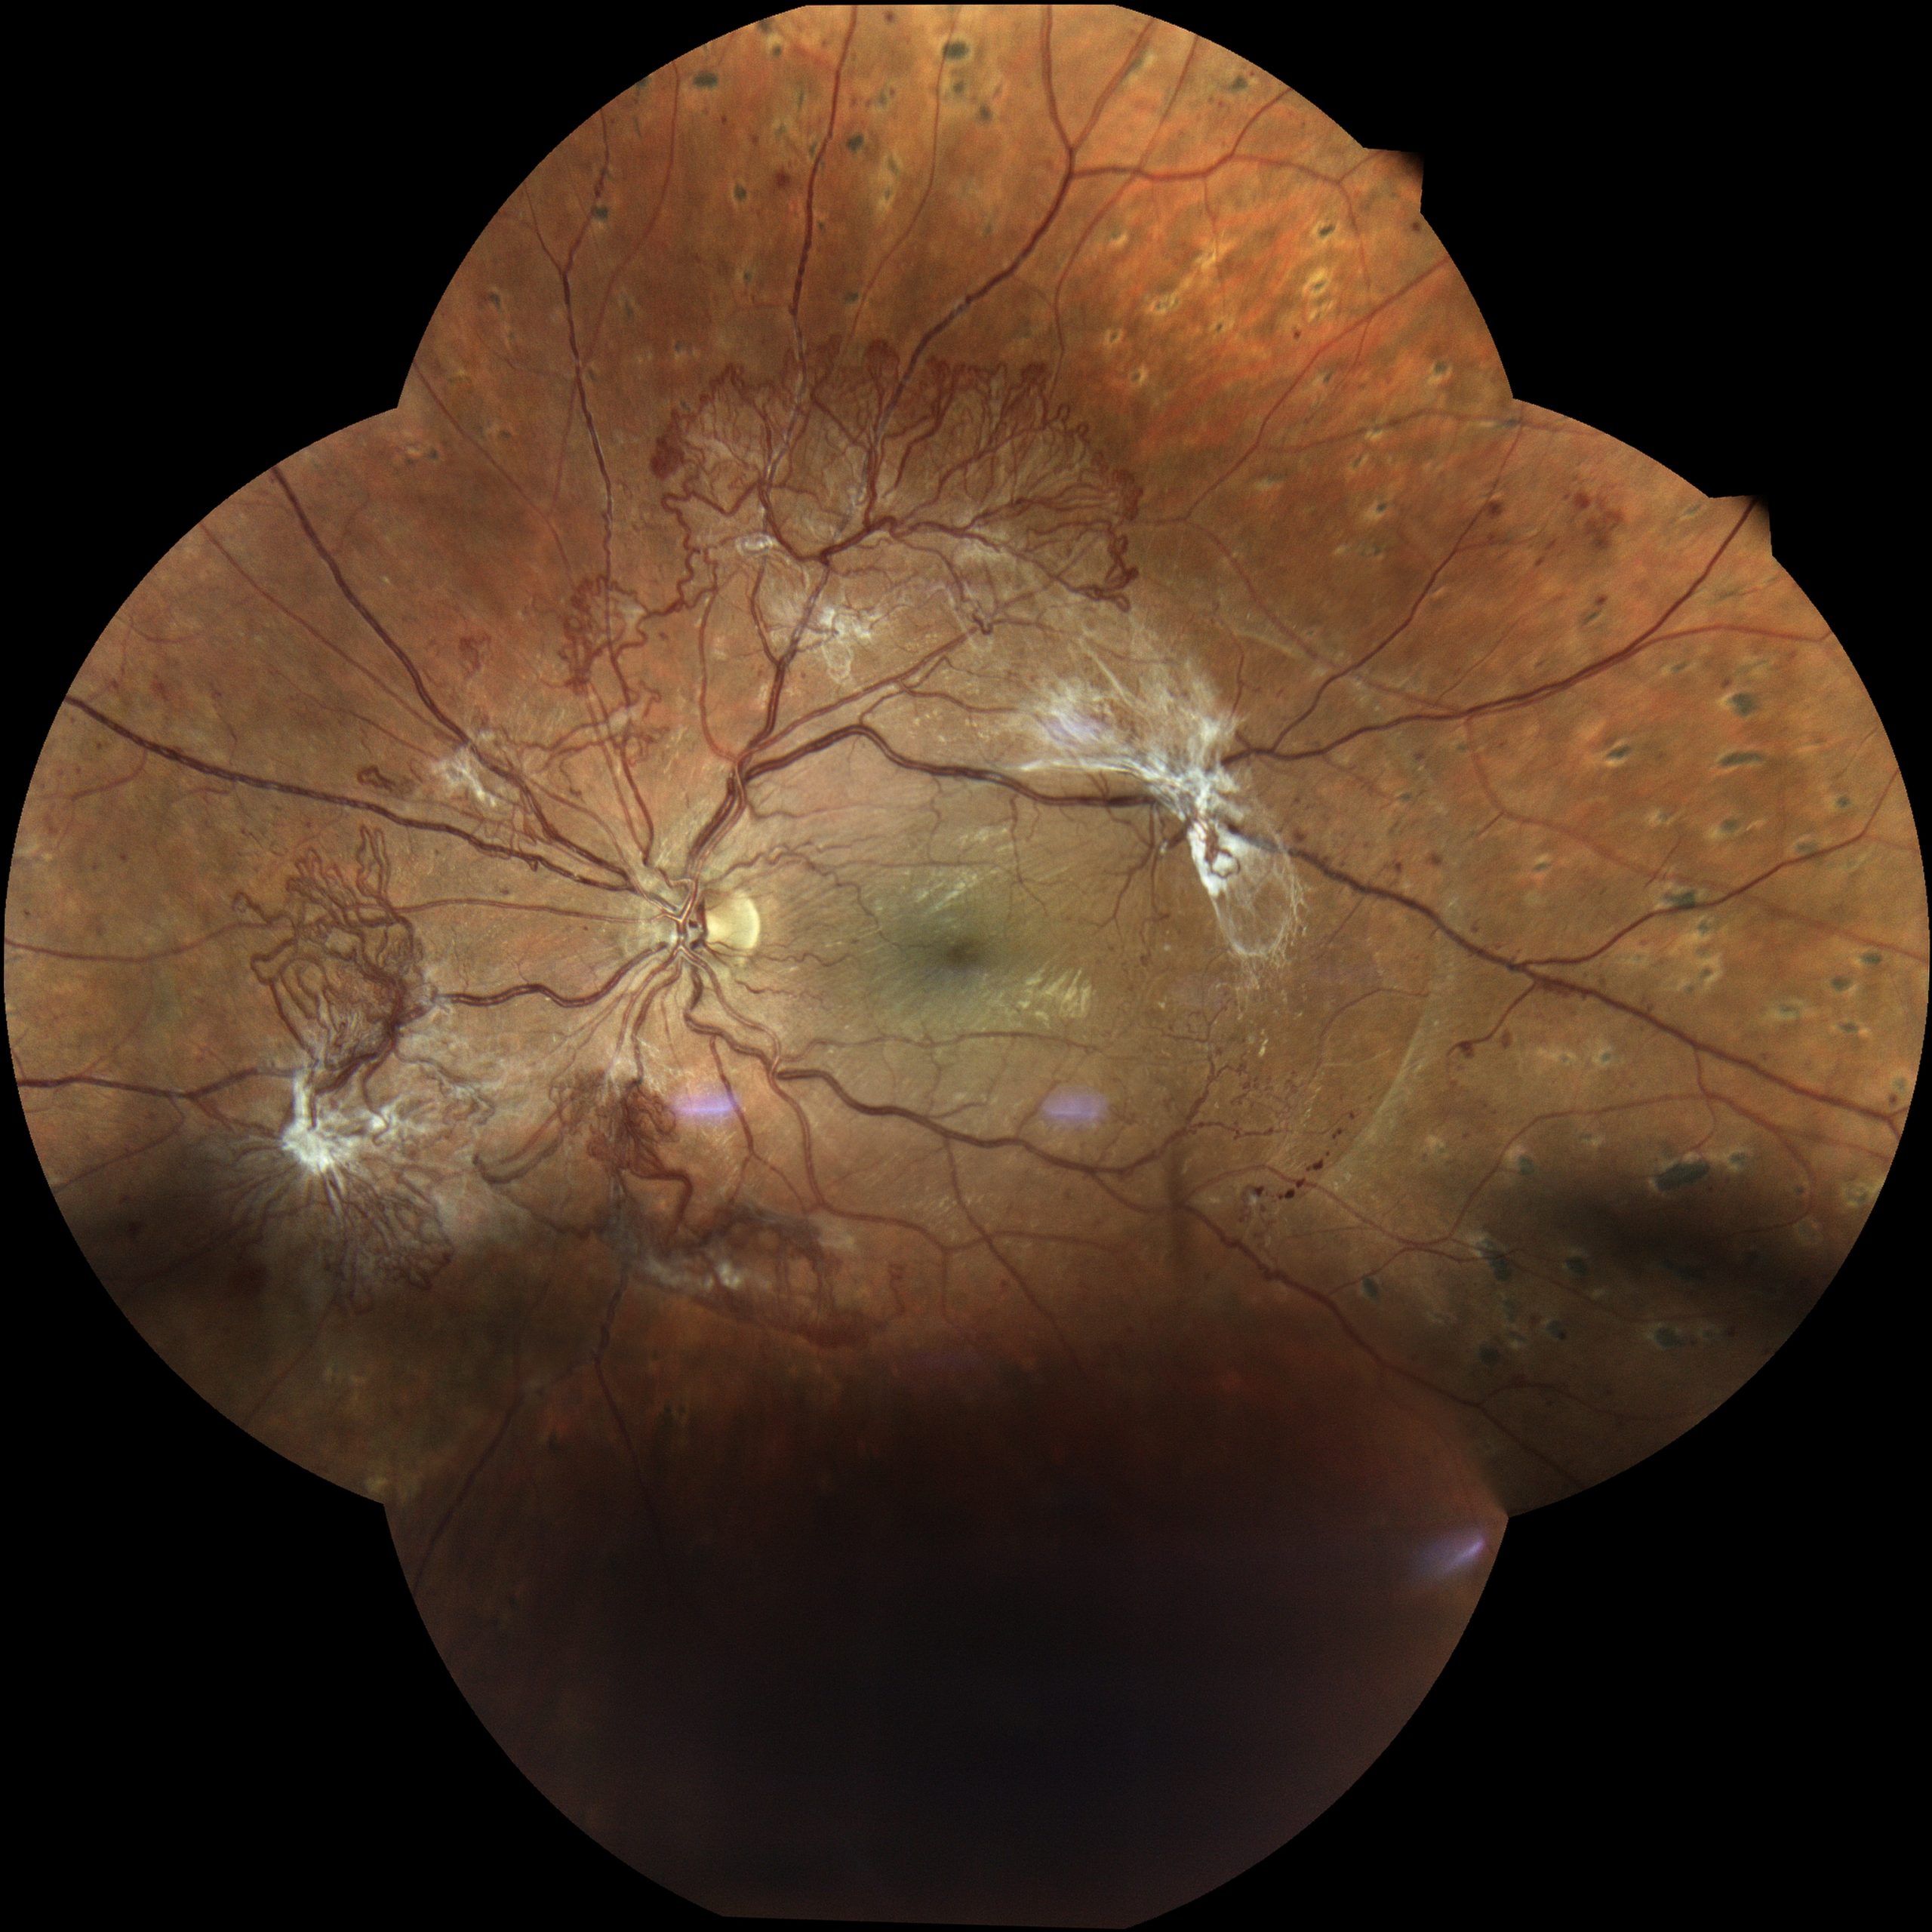

Abbildung 3: Dies ist ein Foto der Netzhaut eines Patienten mit proliferativer Diabetischer Retinopathie. In der Mitte des Bildes ist die Stelle des schärfsten Sehens zu sehen (Makula), links davon der Sehnervenkopf (Papille), noch weiter links, zur Nase hin, finden sich Gefäßneubildungen (Neovaskularisationen).

Abbildung 4: Sechs Monate später haben die Neovaskularisationen massiv zugenommen, ebenso vitreomakuläre Traktionen. Das heißt, aufgrund von Veränderungen im Glaskörper des Auges wird Zug auf die Netzhaut ausgeübt. Die Gefahr einer Netzhautablösung nimmt zu.